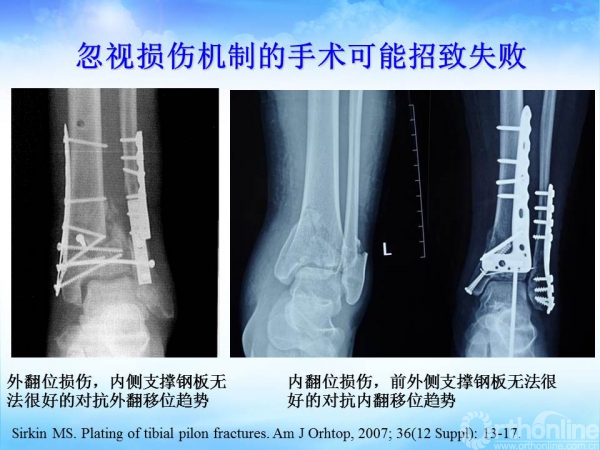

2015-01-13 文章来源:广州军区武汉总医院骨科 蔡贤华 魏世隽 我要说